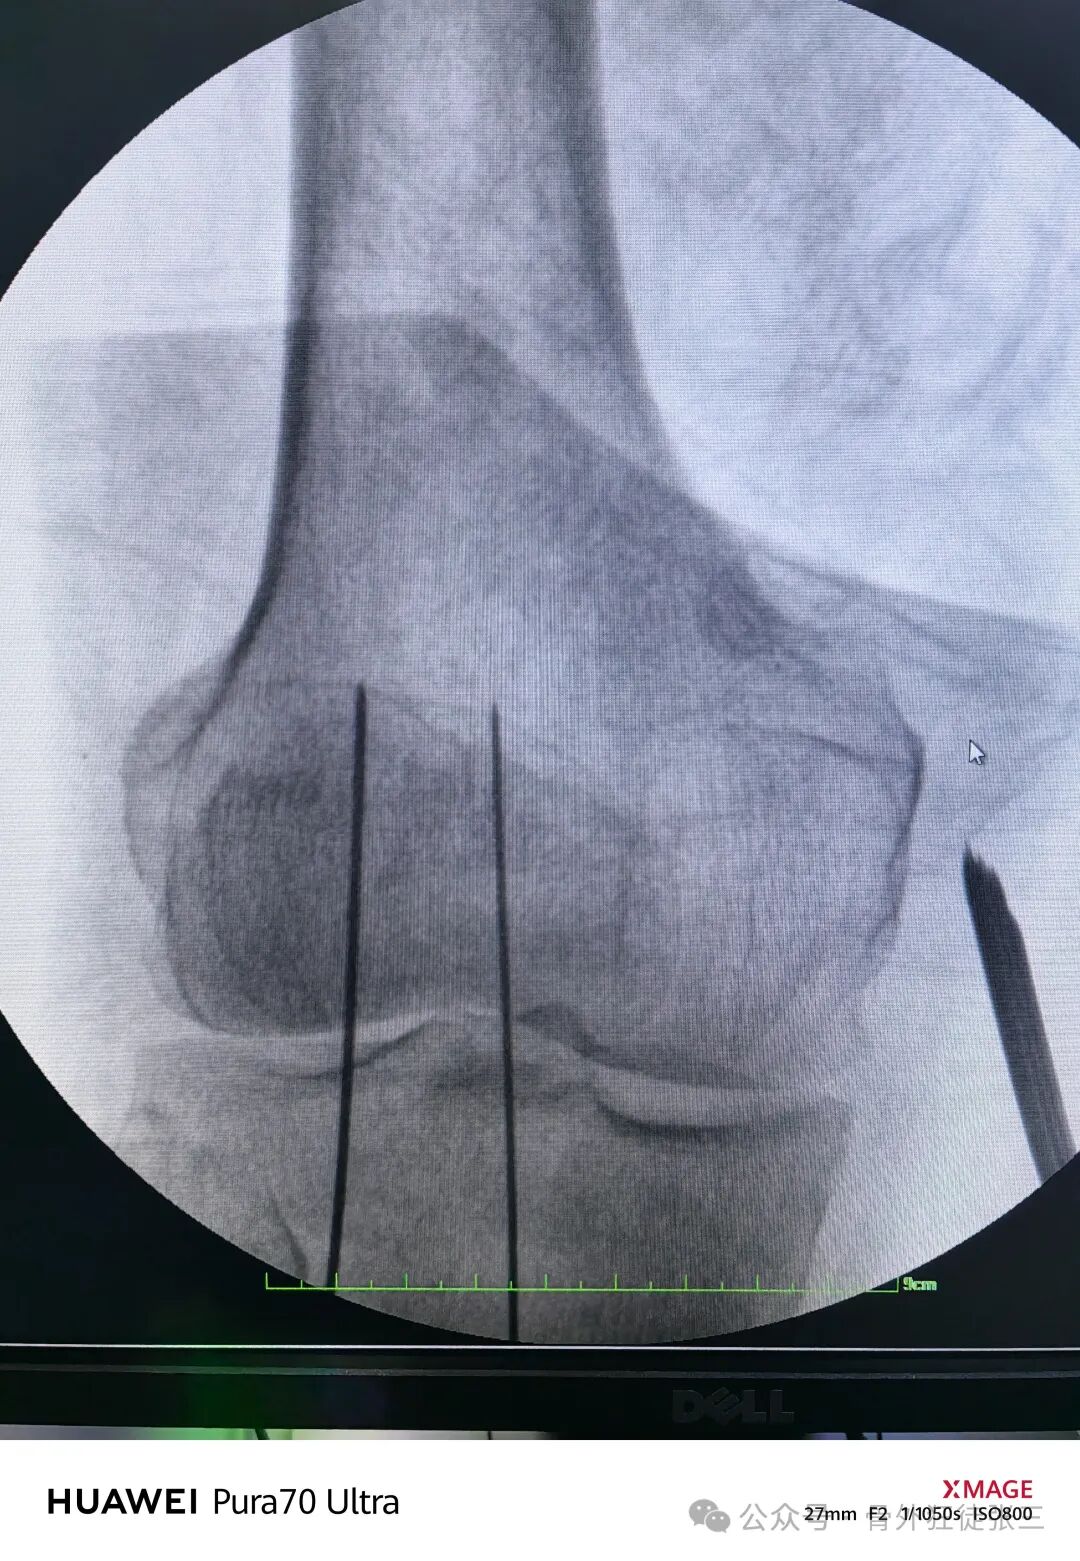

空心钻钻孔后

-

拧入4.5mmx35mm全螺纹螺钉

术后第2天下床行走

患者膝关节主动活动度0度~110度